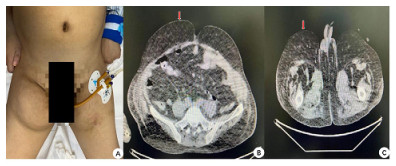

入院查体:患者呈昏迷状,双侧瞳孔等大等圆,直径3 mm,对光反射迟钝,颈部(图 1)和肩部(图 2)分别可见7 cm×4 cm及5 cm×6 cm大小软组织肿胀,质软,腹部及双侧大腿内侧(图 3)可见5 cm×6 cm软组织肿胀,质软,双肺呼吸音粗,双肺可闻及少许湿啰音,心律齐,各瓣膜听诊区未闻及病理性杂音,腹部膨隆,腹部查体不配合。入院后相关检查见表 1,腹部超声提示脂肪肝,心脏超声示左室壁运动弥漫性减低、左室壁肥厚,左室射血分数47%。

| A:患者腹部及双侧大腿内侧对称性脂肪隆起;B:下腹部CT平扫(轴位-下腹部皮下脂肪影增多);C:患者下腹部CT平扫(轴位-双侧大腿内侧皮下脂肪影增多) 图 3 患者下腹部及双侧大腿内侧病变(红色箭头所示) |

入院后给予呼吸机辅助通气,美罗培南抗感染、维生素B1肌注、营养支持等治疗,患者神志逐渐恢复,可自主睁眼,但不能按指令动作,呼吸机条件逐渐下调,并于2月4日成功脱机拔管。复查相关实验室检查见表 2,行头颅CT示脑室系统扩大,脑沟、脑裂稍宽,脱髓鞘改变;颈部CT示颈部大量脂肪沉积(图 1、图 2);胸部CT示双肺散在斑片影,考虑感染;腹部CT示腹腔及皮下脂肪影增多(图 3)。结合患者既往长期大量饮酒史、查体及影像学表现,考虑诊断:马德龙病、Wernicke脑病。患者不能配合指令动作,未行头颅磁共振检查。